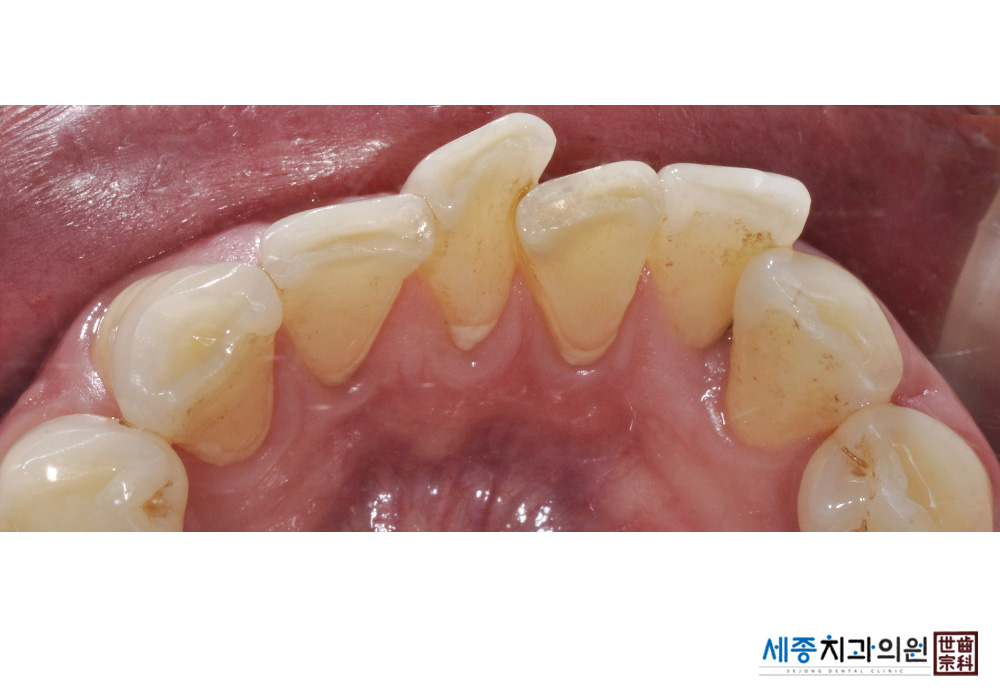

[스케일링] 치주질환 예방 스케일링

치료전 : 2020-01-22

치료후 : 2020-01-22

가글마취&저주파 스켈러를 사용한 스케일링